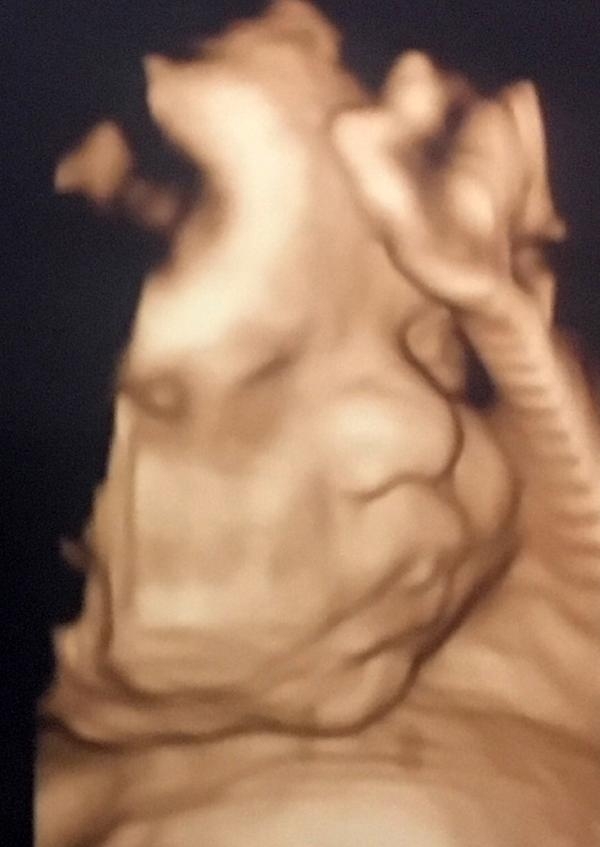

Anne karnındaki bebeklerin gülümseten pozları

Güzel bir pozun yakalanmasının birkaç muayenede mümkün olabileceğini belirten Opr. Dr. Aksu, "Bebeklerin el ve ayakları genellikle yüzlerinin önünde olduğu için her zaman güzel pozlarını yakalayamayabiliriz" dedi.